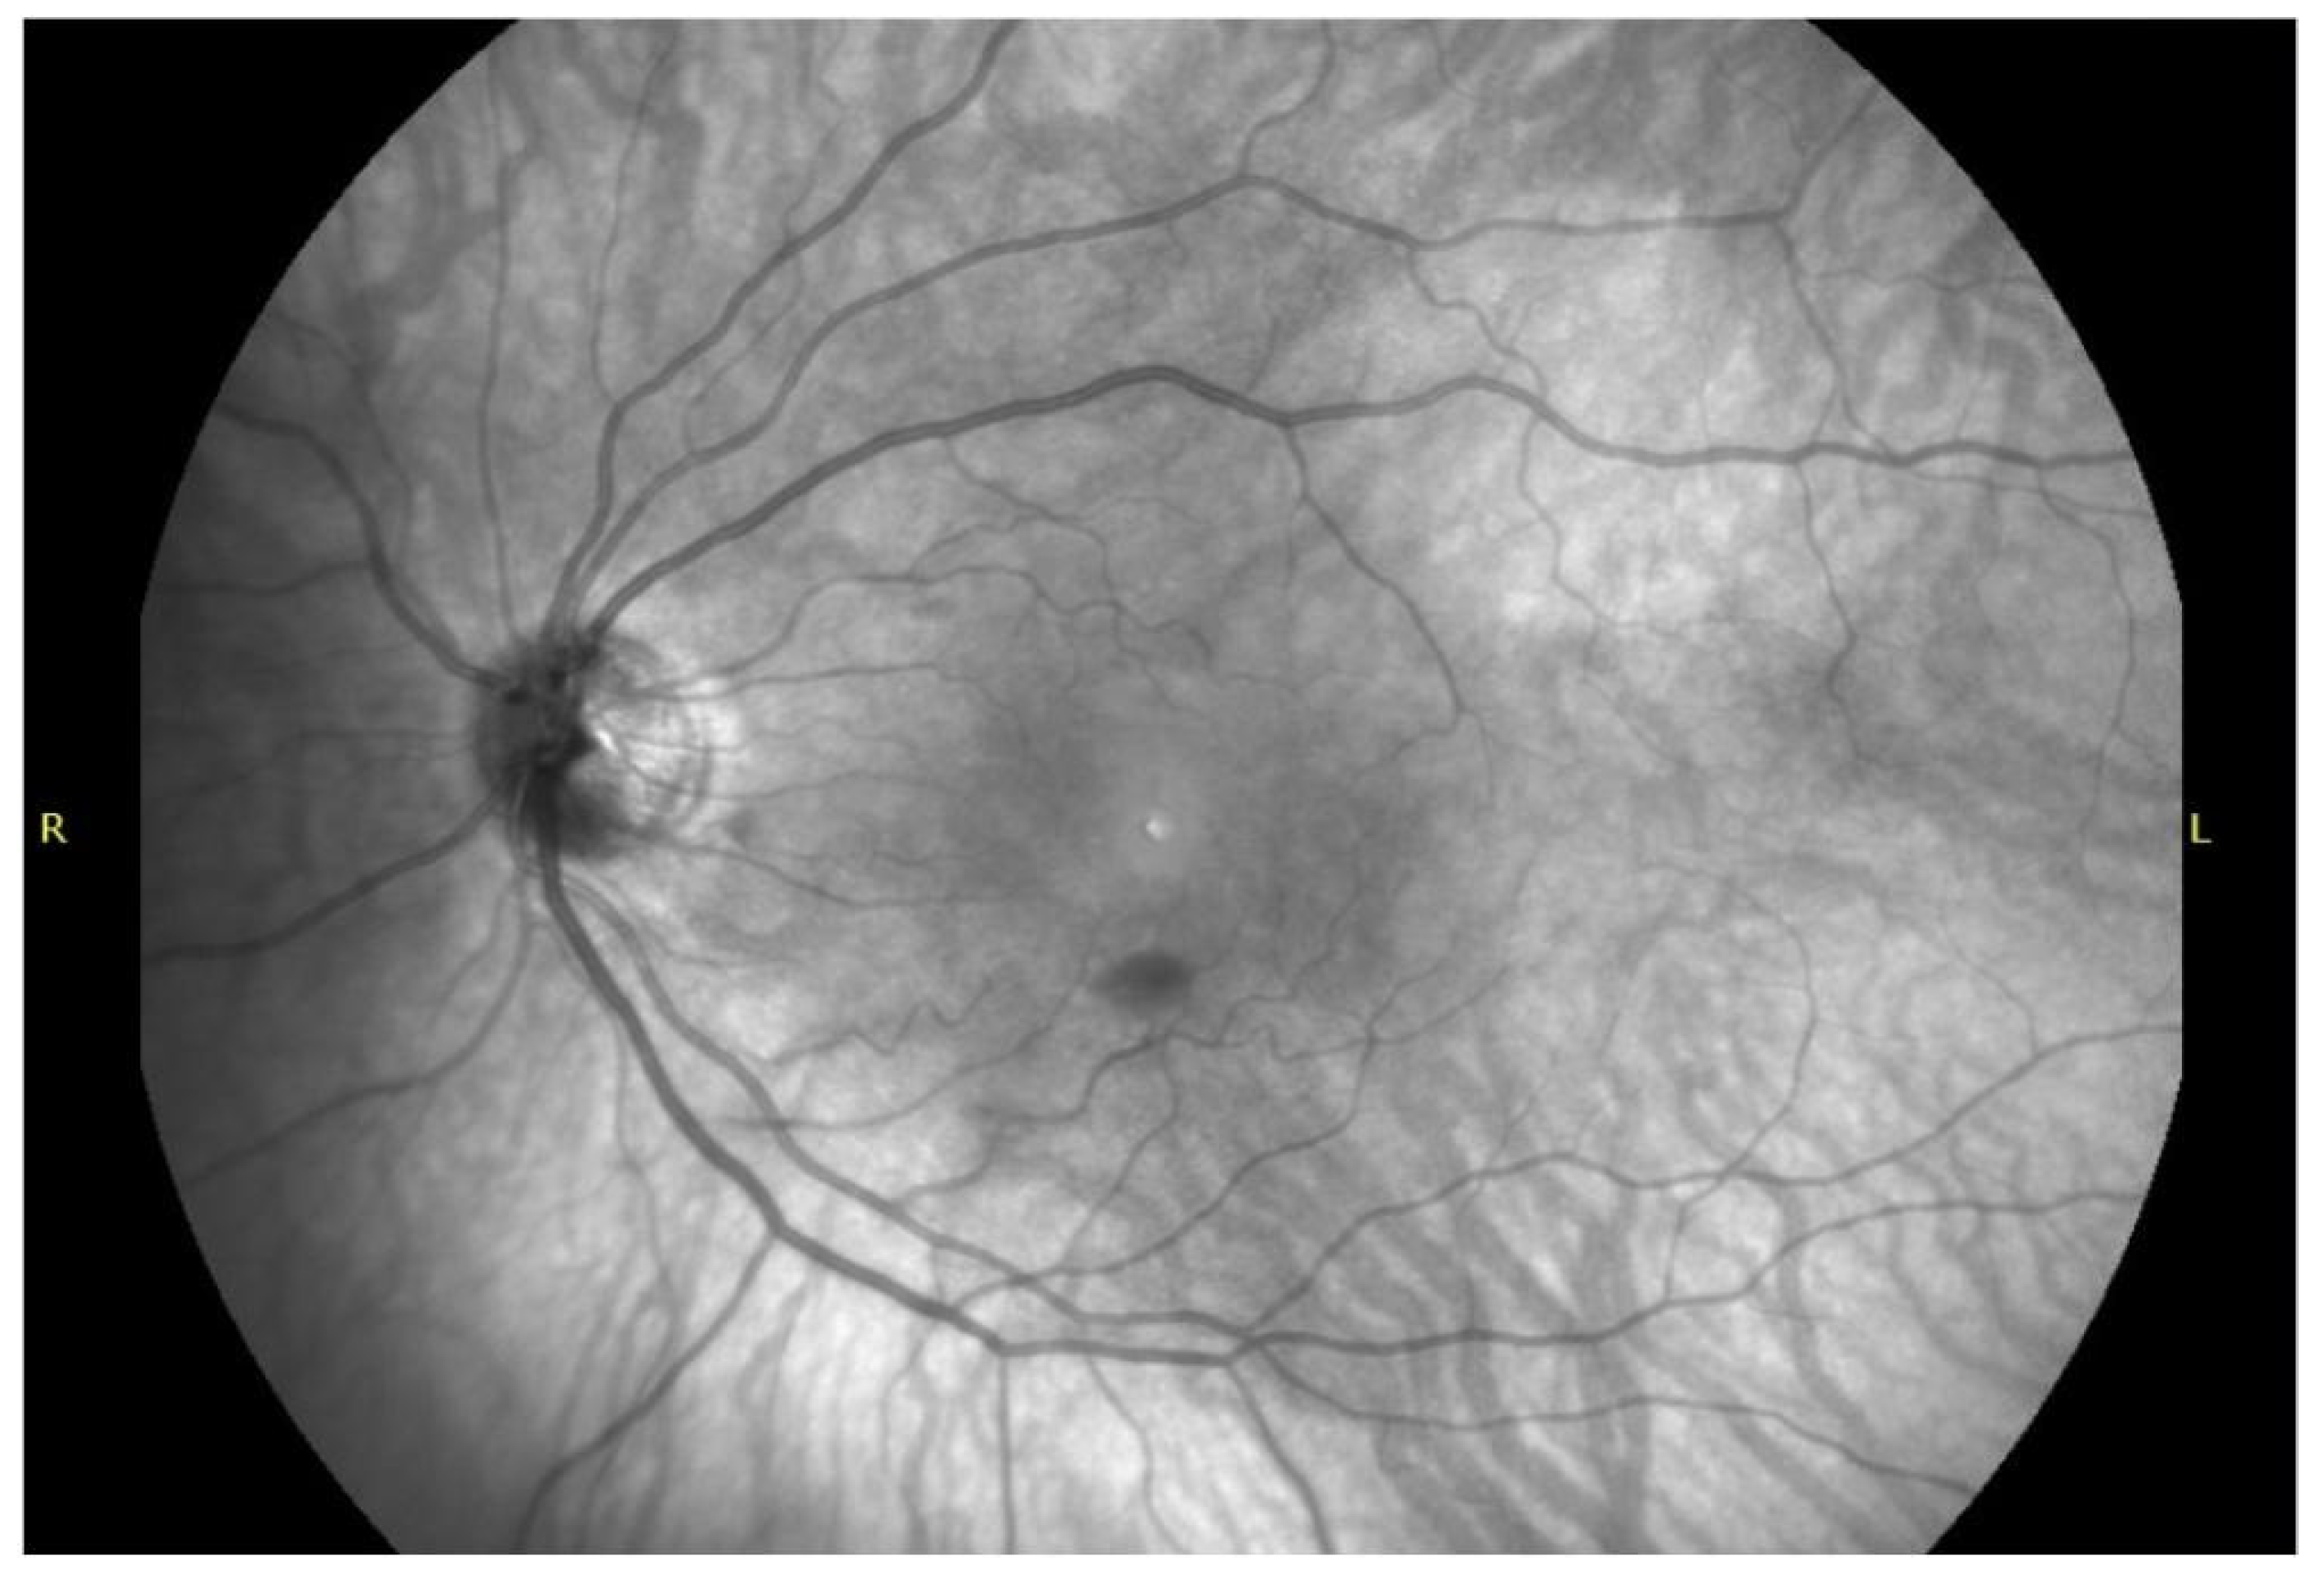

4.2. Autofluorescence, Fluorescein Angiography and Near-Infrared Signatures

4.3. Imaging Biomarkers of Hemoglobin Breakdown and Chronology